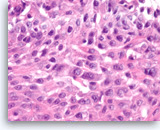

Ductal adenocarcinoma #1,

Pancreas FNA, Cell Block.

The tumor cells are pleomorphic and form poorly organized glands of variable sizes. Some of the glands are fused together. Prominent intracytoplasmic mucin is present.

40X

Ductal adenocarcinoma #1,

Pancreas FNA, Cell Block.

The tumor cells are pleomorphic and form poorly organized glands of variable sizes. Some of the glands are fused together. Prominent intracytoplasmic mucin is present.

40X